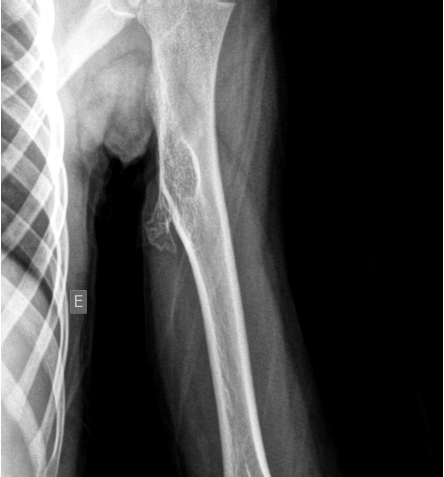

Criança de 5 anos, feminina, apresenta no exame físico área de entumescimento de partes moles no aspecto medial do terço proximal do úmero esquerdo com sinais de estar fixa aos planos profundos e livre em relação à pele e ao subcutâneo, sem sinais flogísticos e quase indolor.

Segue-se imagens de US e Rx do segmento corpóreo.

O quadro clínico e imagenológico sugere